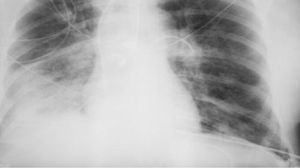

وتقول: "الأشعة السينية هي إشعاع كهرومغناطيسي، مثل الأشعة فوق البنفسجية والضوء والحرارة. صحيح قد تلحق جرعاتها العالية الضرر بالخلايا، كالذي تسببه حروق الشمس. وأن الاستلقاء تحت أشعة الشمس على الشاطئ دون حماية أخطر بكثير من تصوير بالأشعة السينية للصدر مرة واحدة سنويًا".

وتؤكد بلاتونوفا أن عدم اكتشاف المرض أخطر بكثير من الخضوع للأشعة السينية، حيث تقلل المعدات الحديثة من المخاطر، كما أن الفحوصات في الوقت المناسب تسمح بالكشف السريع عن الأمراض وبدء العلاج.